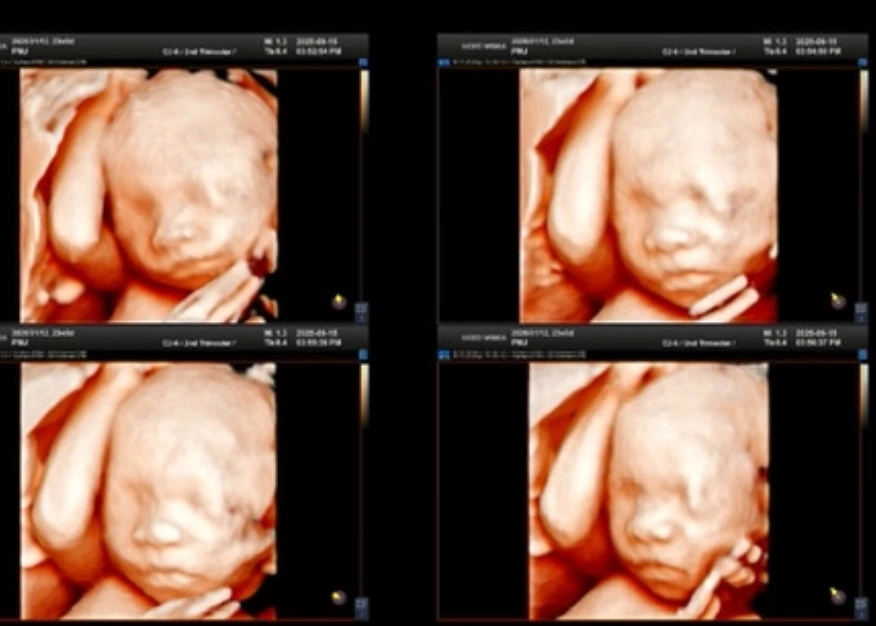

인생네컷 정밀초음파

우리아기, 이렇게 생겼구나!

초음파선생님이 감사하게도 마치 입체초음파처럼 낭만이를 보여주셨다. 임신 기간 중 이 사진을 제일 많이 본 것 같다. 사랑스러워 정말~!

오빠랑 나랑 둘다 동글동글한 얼굴이라 낭만이도 동그라미 공주로 나올 것 같다 하하

검사결과는 다행히 아무 문제가 없었다.